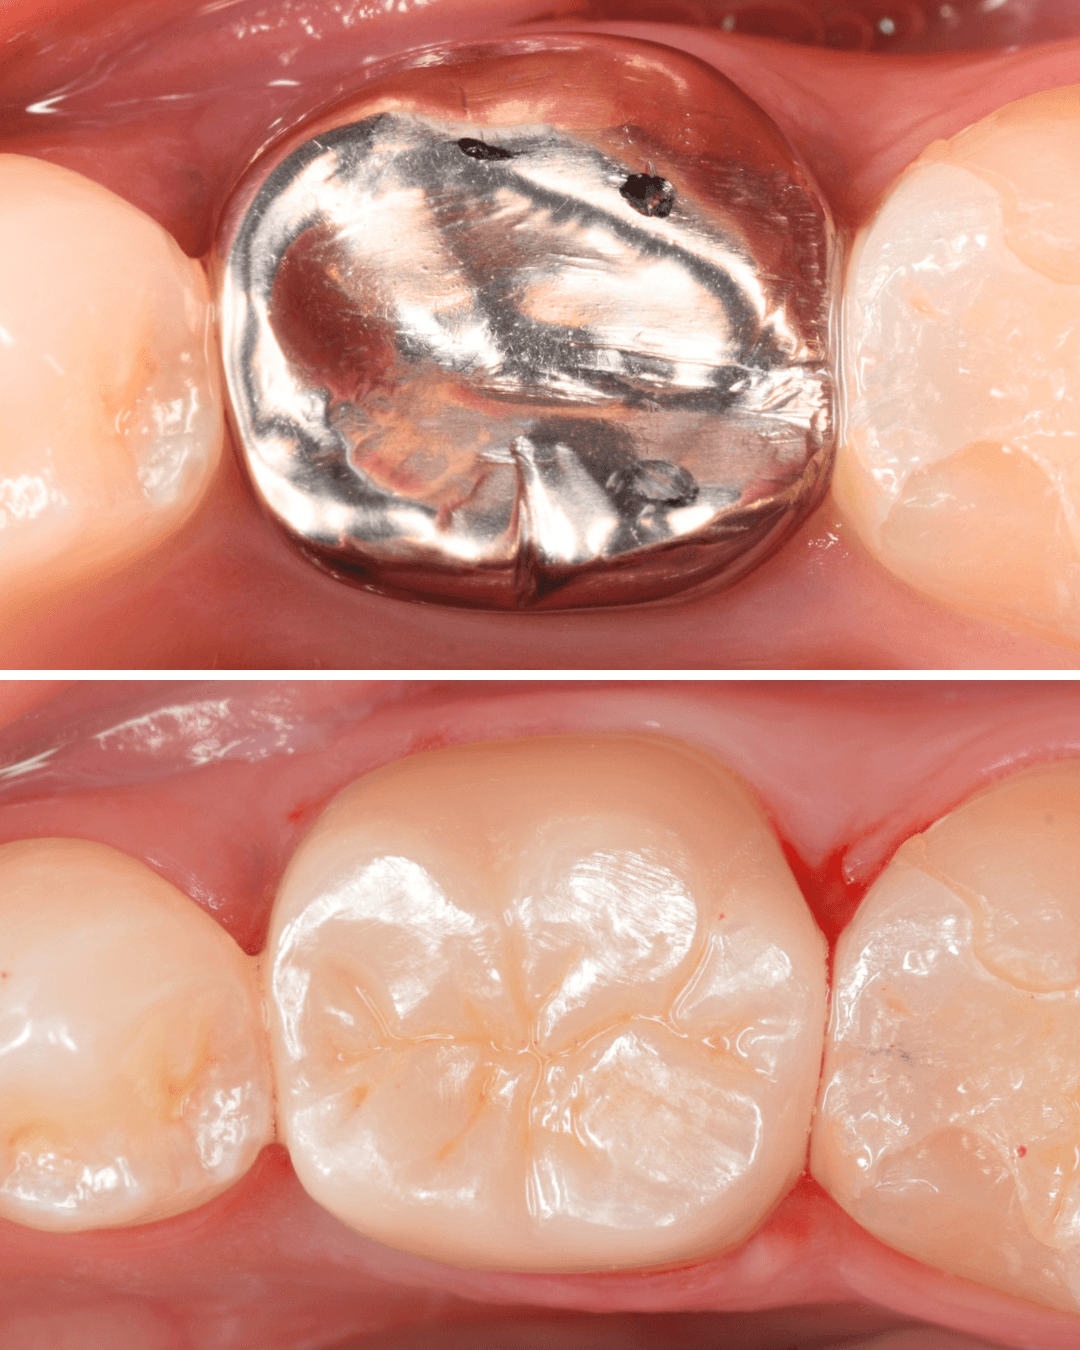

Case.12 銀歯を再治療、白い歯へ

定期メンテナンスに受診中の患者さんです。

奥歯の銀歯が気になるので、セラミックに変えたいとのご希望でした。

最近は、つめものだけでなくさし歯のやり替えの希望も増えていますね。

こちらは、(オール)ジルコニアクラウンでの治療を進める事になりました。

治療前後の比較です。

患者さんにも、印象が変わったとおっしゃっていただきました。